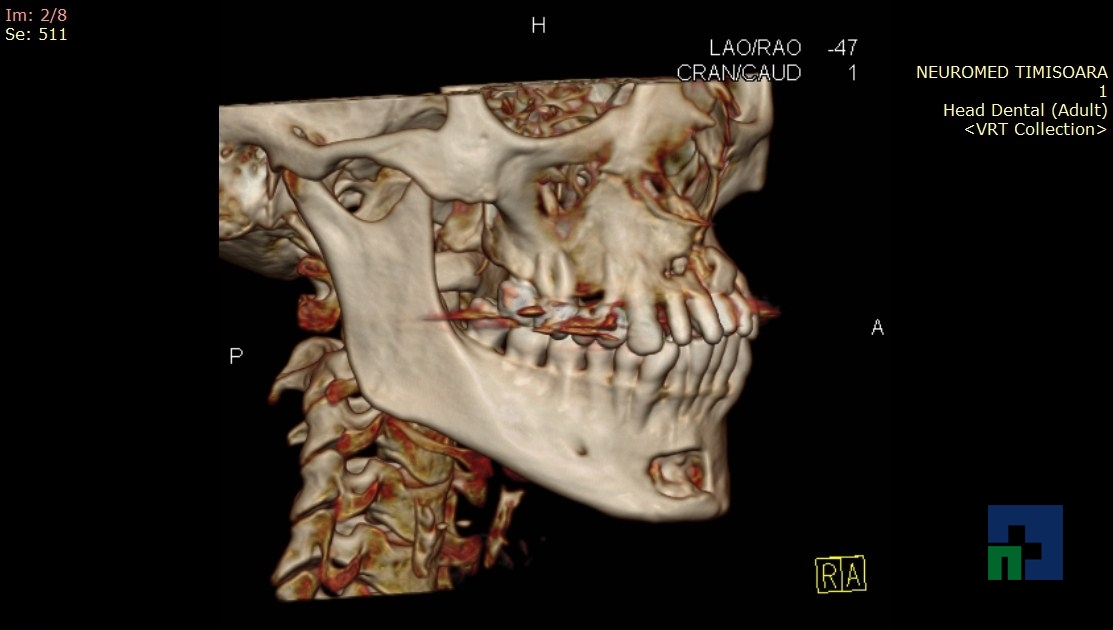

- Diagnosticul fracturilor:

-

- Unice

- Multiple

- Cu înfundare

- Complexe cranio-sinusale

- Complexe cranio-etmoidale

- Complexe cranio-orbitare

- Complexe cranio-faciale